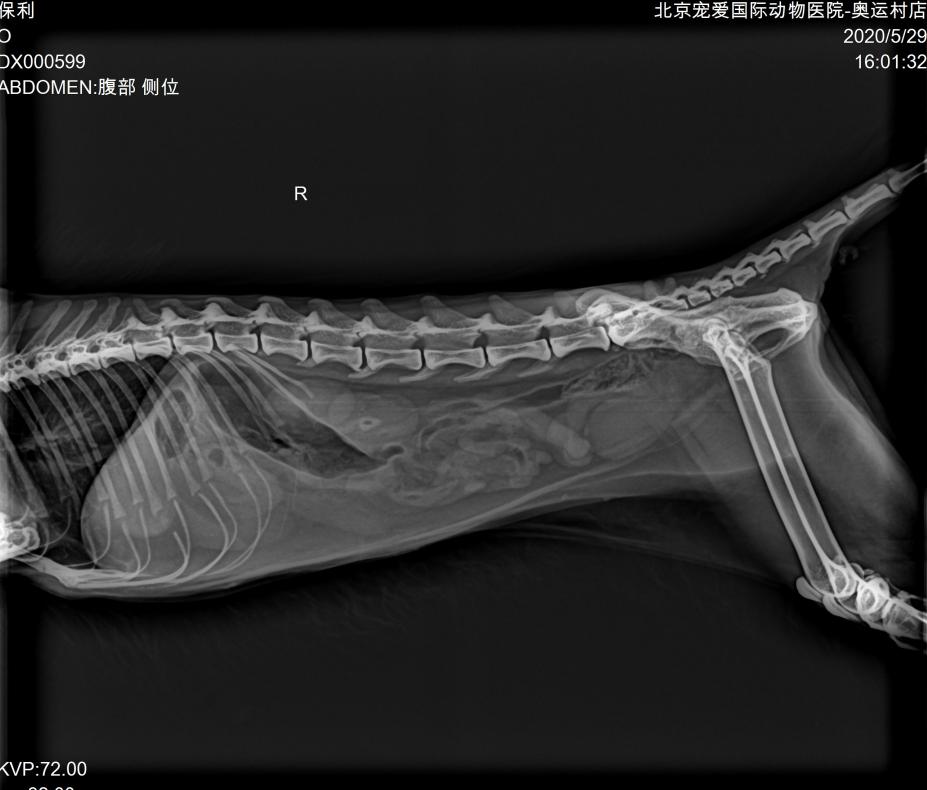

DR:

DR显示胃肠道空虚,未见阳性异物。